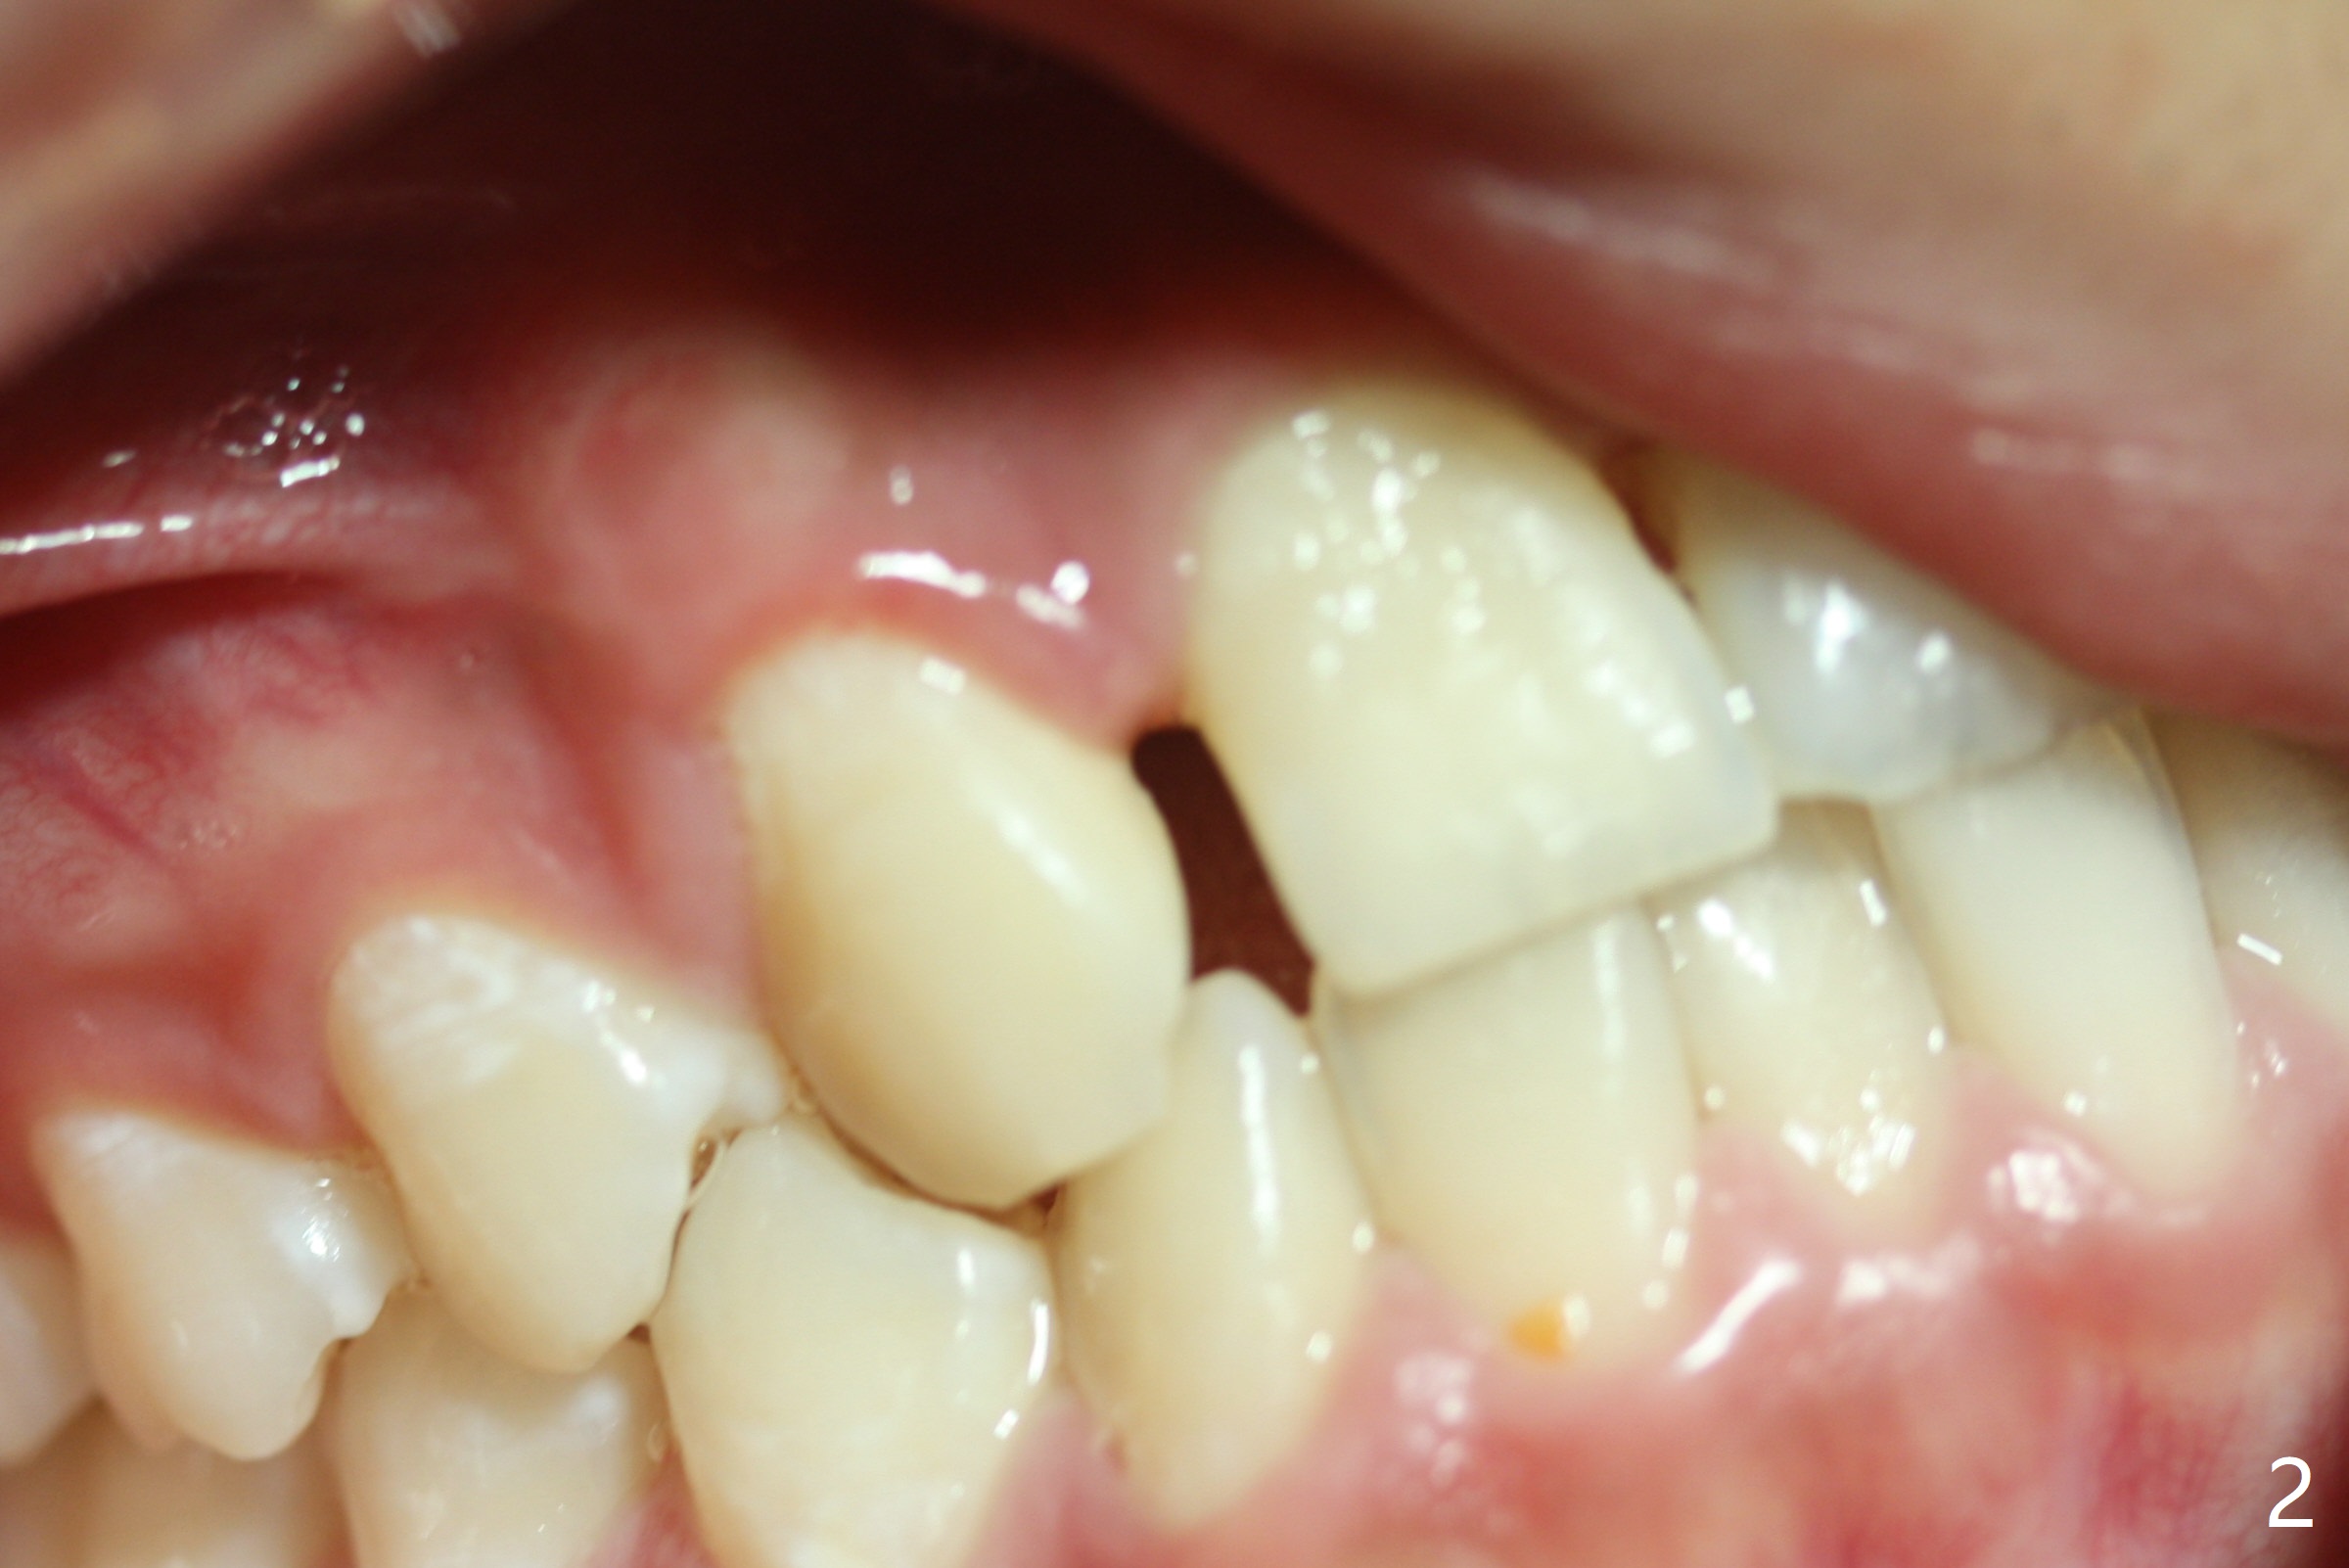

A 14-year-old man requests ortho because of crowding lower anterior and UR missing lateral (Fig.1-4). Open space for the future implant at UR2 will correct upper midline deviation (Fig.1) and change Class II malocclusion to I on the right (Fig.6, as compared to Fig.7). To control UR1,3 root torque, bracketing on these 2 teeth will be intentionally off (Fig.5). The treatment will take ~ 2 years. Prior to implantation at UR2, what type of prosthesis should be made?